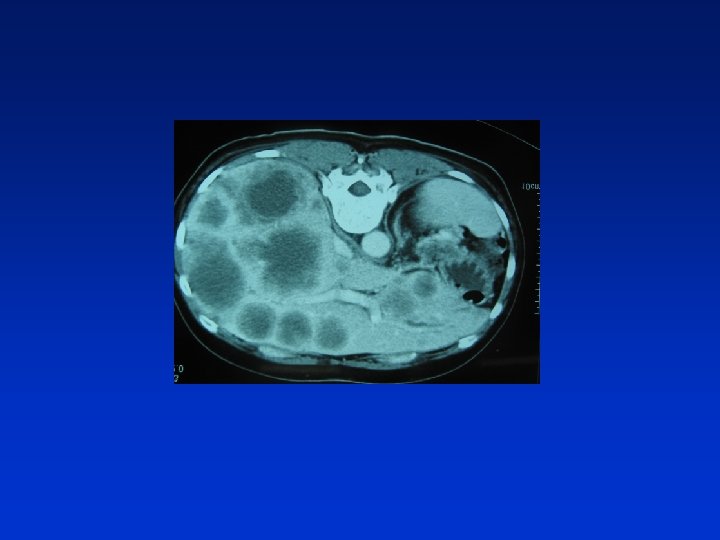

증례 3 51세 여자 진단명 : Pancreas tail cancer 주소 : Pain on right upper abdomen, dull, continuous 현 병력 : 2002년 12월 상기 질환 진단, 복통으로 MS contin 20 mg PO, every 12 hours로 조절 중 통증이 심해져서 입원 검사실 검사 소견 : CBC : Hb 7. 9 g/d. L , WBC 3, 600 (Seg. N 52%), PLT 123, 000 /u. L Blood Chemistry : WNL

진 단 Abdominal pain due to liver capsule distension by metastatic cancer